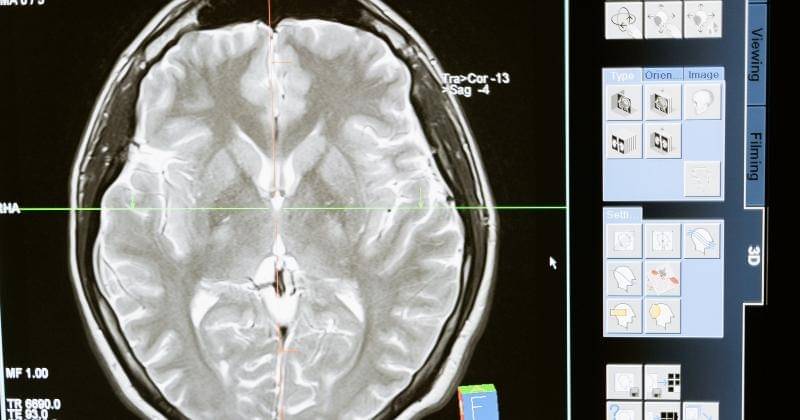

Naegleria fowleri adalah amoeba pemakan otak yang tersebar di area perairan seperti sungai dan danau. Bakteri ini ditemukan pertama kali pada tahun 1965. Ia masuk melalui hidung yang kemudian berjalan ke otak. Infeksi ini menyebabkan kematian setelah gejala-gejala awal yang dialami penderitanya mulai dari sakit kepala hebat, demam, mual, muntah, dan leher kaku. Perlu diketahui bahwa penyebarannya tidak terjadi antara manusia dengan manusia.